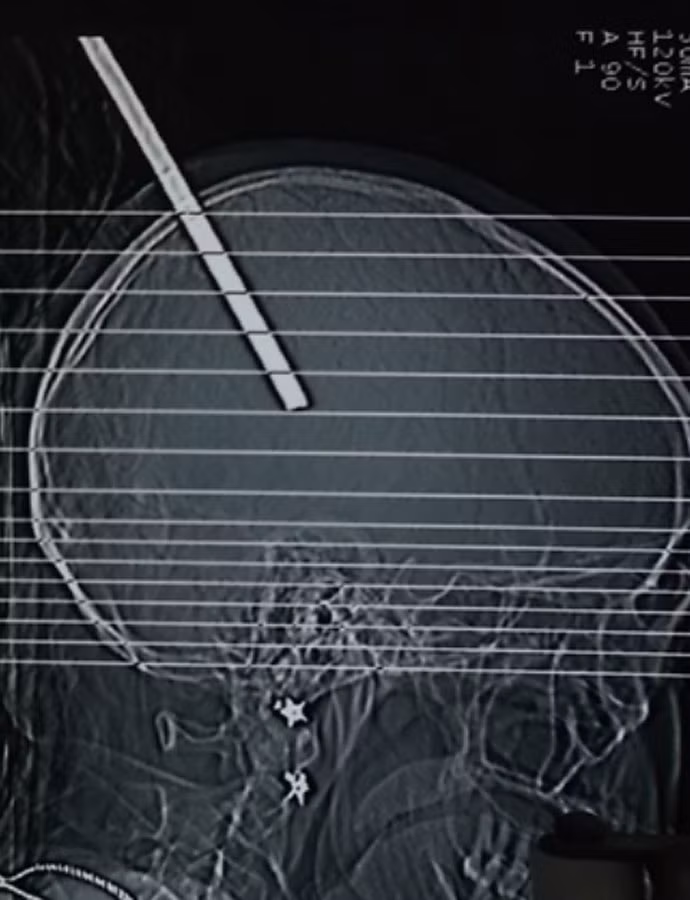

Phim chụp cây sắt đâm xuyên vào hộp sọ của bệnh nhân. Ảnh: Bình Nguyên

Đây được xem là ca bệnh hy hữu nhất từ trước đến nay tại Bệnh viện Đa khoa tỉnh Khánh Hòa. Theo đó, bệnh nhân Nguyễn Thị Khánh Trang, 31 tuổi, trú tại thành phố Nha Trang, tỉnh Khánh Hòa phải nhập viện khẩn cấp trưa 14-11 do bị một cây sắt có đường kính 6 mm, dài 20,5 cm rơi trúng vào đỉnh đầu, xuyên vào hộp sọ gần hơn 10 cm. Chị Trang bị tai nạn trên khi đang lao động tại công trường xây dựng vào buổi sáng cùng ngày.

Bác sĩ Trần Văn Đại Dương-mổ chính trong kíp mổ, cho biết: Ngay sau khi bệnh nhân Nguyễn Thị Khánh Trang nhập viện, kíp mổ đã tiến hành phẫu thuật ngay. Do tính chất phức tạp của ca bệnh nên ca mổ đã phải kéo dài trong 3 giờ liên tục. Khi lấy được cây sắt ra khỏi đầu của chị Trang thì mô não bị lòi ra ngoài. Kíp mổ phải mở hộp sọ để cầm máu, loại bỏ phần mô não bị dập và máu tụ.